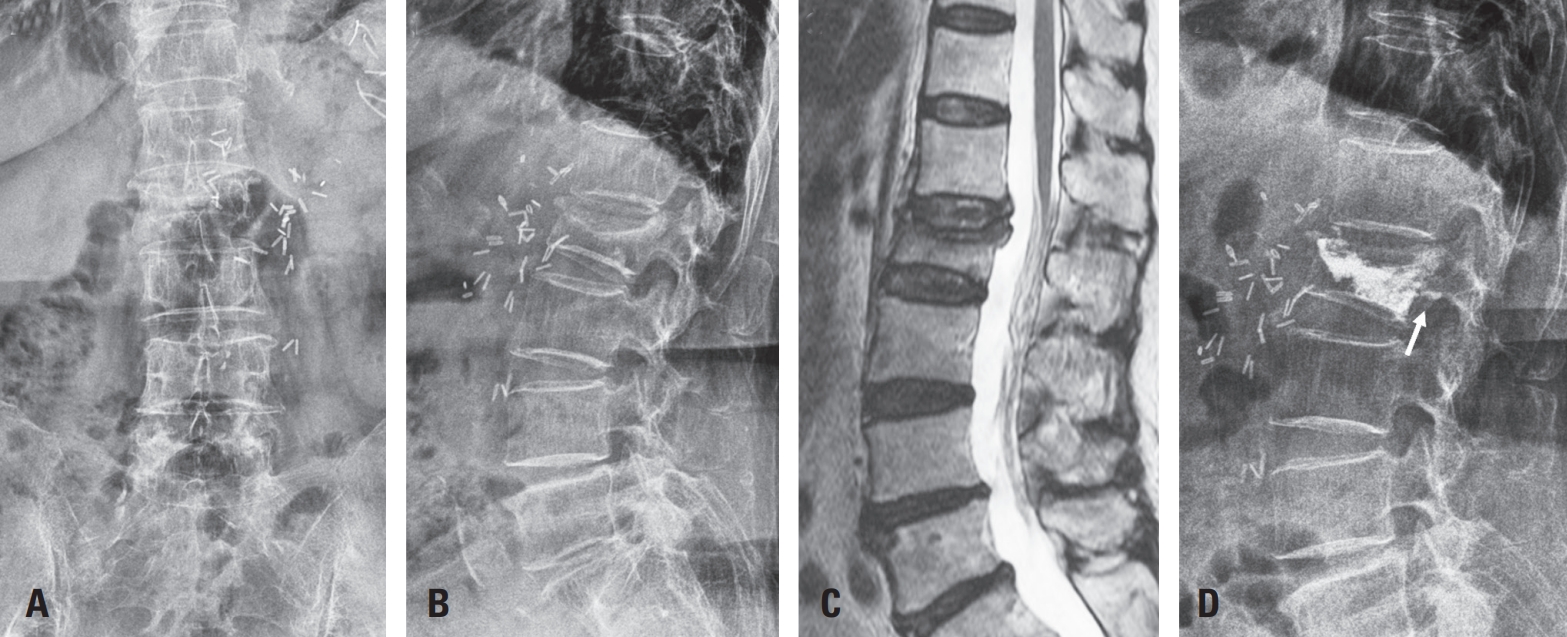

Romosozumab Following Long-Term Bisphosphonate Use for Severe Osteoporotic Vertebral Collapse (Vertebra Plana): Potential Facilitation of Vertebral Fracture Healing

To evaluate the clinical and radiologic effects of switching from long-term bisphosphonate therapy to romosozumab in an elderly patient with severe osteoporosis and vertebra plana–type severe osteoporotic vertebral collapse, followed by transition to denosumab maintenance therapy.

An 85-year-old woman with a history of osteoporotic fractures and prolonged intravenous bisphosphonate therapy presented with an acute L2 compression fracture. Conservative management with a body cast was initiated, and romosozumab was introduced as a switching therapy when anabolic treatment was indicated. Thoracolumbar spine radiographs were obtained at presentation and at 1, 3, 7, and 12 months after injury. Computed tomography was performed at presentation and again at 7 and 12 months to assess fracture consolidation. Bone mineral density (BMD) was measured beginning at 18 months after injury and annually thereafter. Functional assessments were recorded throughout a 30-month follow-up period.

During romosozumab therapy, the L2 vertebra plana–type severe osteoporotic vertebral collapse showed marked radiologic improvement, characterized by progressive intravertebral bone fill-in and gradual restoration of trabecular continuity without further loss of height. Serial follow-up CT and MRI demonstrated consolidation of the previously cavitated vertebral body, indicating substantial structural recovery rather than simple stabilization. Clinically, the patient experienced steady improvement in pain and ambulatory capacity. After completing six monthly doses of romosozumab, therapy was transitioned to denosumab. L2 bone mineral density improved from a T-score of –1.7 to –0.9, accompanied by gains in femoral BMD. No additional fragility fractures occurred throughout the follow-up period.

Switching from long-term bisphosphonate therapy to romosozumab resulted in improved BMD, progressive vertebral bone fill-in, and stabilization without further collapse in this elderly patient with severe osteoporosis. Although not established as a fracture-healing agent, romosozumab may serve as a practical anabolic option in selected cases, with denosumab maintenance ensuring ongoing skeletal protection.